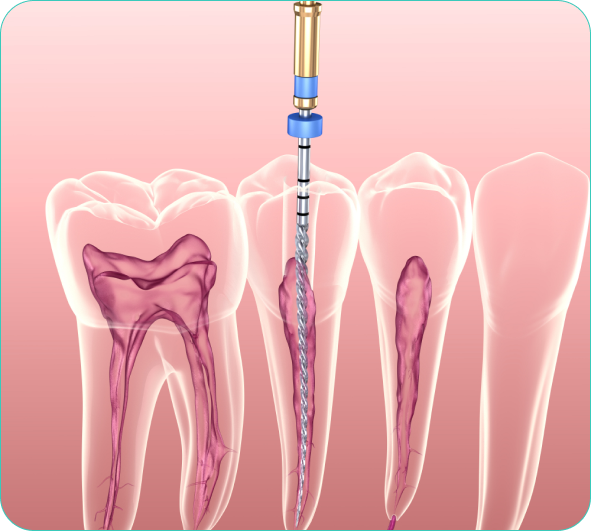

Every tooth is a three-layered structure namely – Enamel, Dentin & Pulp. If the tooth decay is limited to the first two layers, it can be corrected with Filling/ Restoration. In case the tooth decay reaches the third layer and causes inflammation or infection of pulp, an RCT or Endodontic Treatment is needed.We also provide Single Sitting Root Canal Treatment Using an advanced Endodontic technology Single-sitting Root Canal Treatment is performed within an hour. At Braces Faces Superspeciality dental care, dr.swapnil has performed more than 2000+ RCT with painless injection using modern equipment.Book appointment for painless single sitting RCT